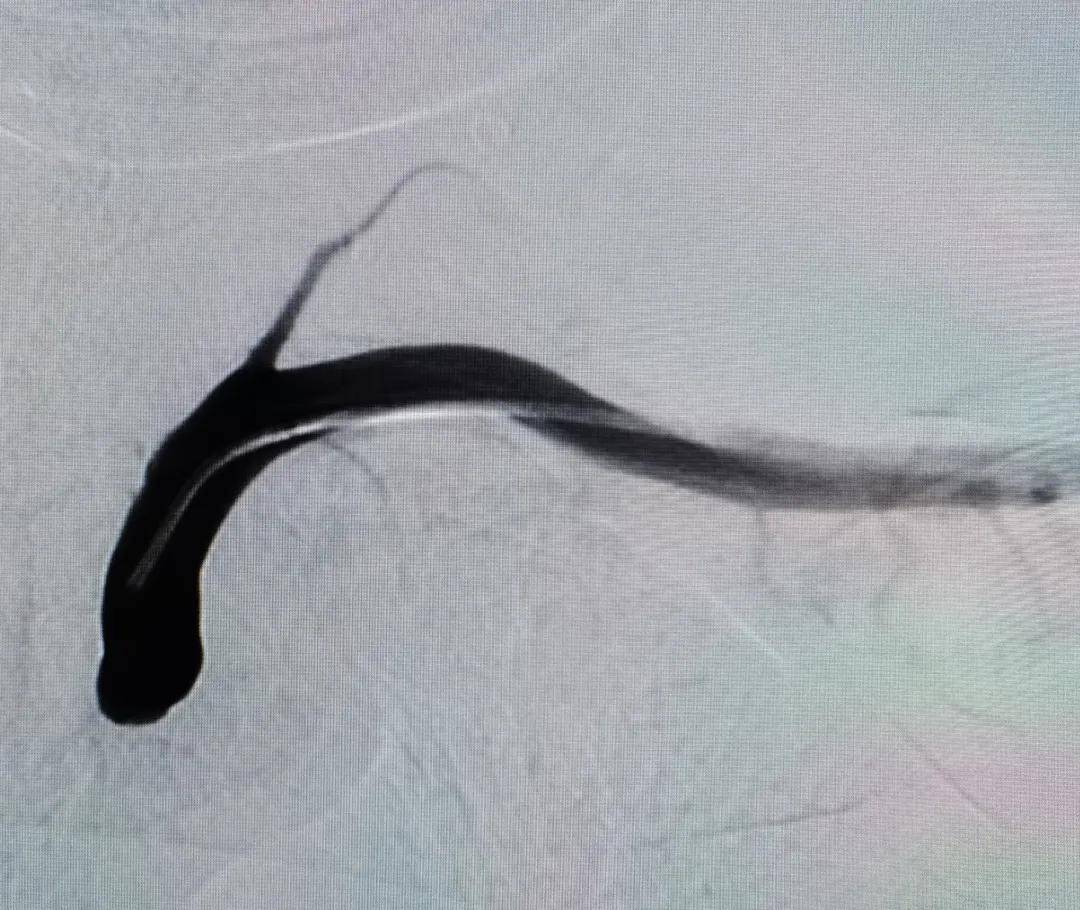

经左侧桡动脉入路造影显示:左侧锁骨下动脉闭塞

术后造影显示左侧锁骨下动脉再通 , 血流完全恢复 术后造影显示左侧锁骨下动脉再通 , 血流完全恢复